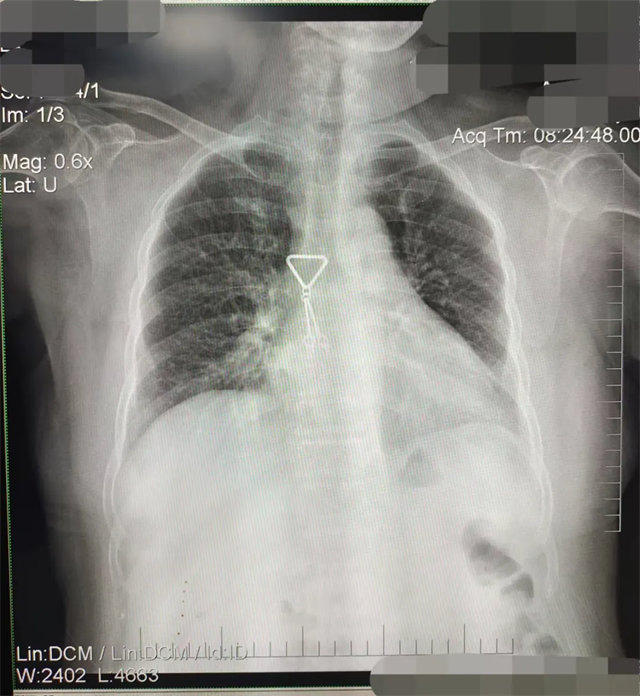

拍攝的不合格胸片的缺陷和解決方法

缺陷:肩胛骨未完全拉離肺野,吸氣不完全,存在金屬偽影遮擋,略有聳肩,且肺尖顯示不好,圖像顆粒感較強,管電流量不夠,信噪比偏低。

解決:去除金屬物品后,按標準體位,使患者雙肩旋前與前胸一并緊貼成像件,適當(dāng)調(diào)高mAs,然后深吸氣后屏氣曝光。